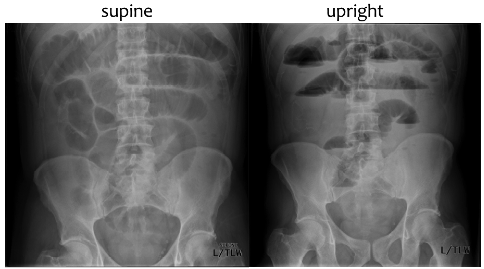

Use Radiography or CT

Supine - Dilated small & large bowel on supine image

Upright - Air fluid levels in small & large bowels and colon (can only be seen on upright and lateral decubitus (not on supine))